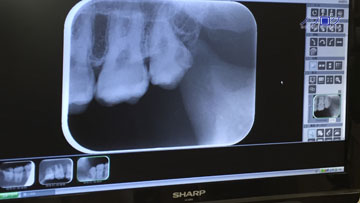

前々から気になっていた親知らず。

右上にあった親知らずは、4年ほど前に抜歯していた。

今度は左上の親知らずが欠けた。

やはり、磨きにくい親知らずは虫歯になりやすい。

それに、歯の生え方、かみ合わせもうまくない。

ということで、全て抜歯という方向で進行中。

まずは、左上の親知らずを抜き、次に右下の親知らずを抜く。

ただ、若干根っこが曲がっているらしい。